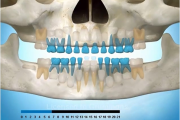

Esimeste molaaride (purihammaste) lõikumine. 1. molaaride ektoopilise lõikumise jälgimine. Ülemised ja alumised esimesed purihambad e. molaarid lõikuvad orienteeruvalt6-7-aastaselt piimahammaste rea lõppu. Enamasti lõikuvad samanimelised jäävhambad paaridena. Normaalne lõikumise Loe edasi »

- valehambumus (18)